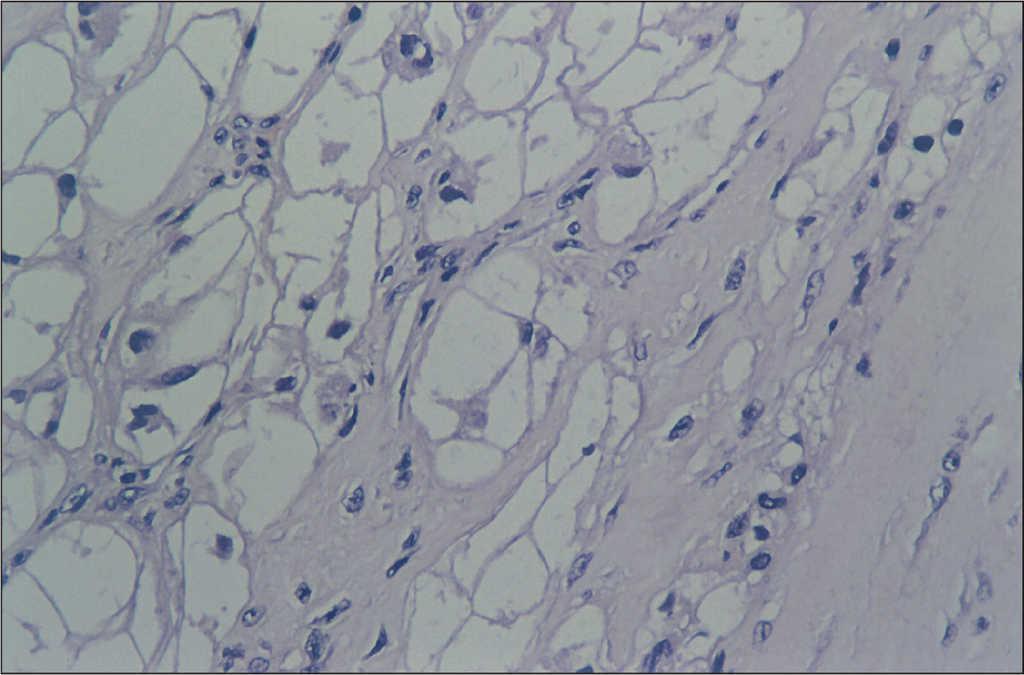

A partir de las 24 h se observan crisis convulsivas clónicas generalizadas con electroencefalograma patológico crisis focal motora en el hemisferio izquierdo con posterior descarga subclínica en el mismo hemisferio que desaparece con diazepam, fenobarbital y anticonvulsivantes. Actividad de fondo deprimida. En los controles posteriores se observan dos descargas irritativas subclínicas en región frontal en forma de onda lenta regular de unos segundos de duración, y otra de onda lenta aguda en región temporal. Extubación a los 4 días. A los 10 días se realiza tomografía computarizada craneal: en zona subependimaria lesión puntiforme en posición posterior del asta frontal del ventrículo derecho lateral derecho por encima del agujero de Monro, que pudiera corresponder a un pequeño hamartoma. Hipodensidad bilateral y simétrica en la zona posterior de los lóbulos temporal, occipital y parietal. Se produjo hemorragia parietal que le provocó ceguera cortical que cedió 10 meses después. A partir de los 18 días el EEG fue normal. El ecocardiograma mostraba ausencia de tumor en la zona subaórtica. Válvula aórtica normal. El eco-Doppler reveló gradiente máximo en el tracto de salida del ventrículo izquierdo de 16 mmHg. En el estudio anatomopatológico microscópico se encontraron células en araña con masa citoplasmática central y núcleos excéntricos. Imágenes radiales hasta la periferia (fig. 2). Los citoplasmas contenían gránulos de glucógeno y la masa citoplasmática contiene mitocondrias, miofibrillas y septofibrillas con bandas en Z. Fue dado de alta un año después de la intervención.

Figura 2. Células en araña con masa citoplasmática central y núcleos excéntricos. Imágenes radiales hasta la periferia.